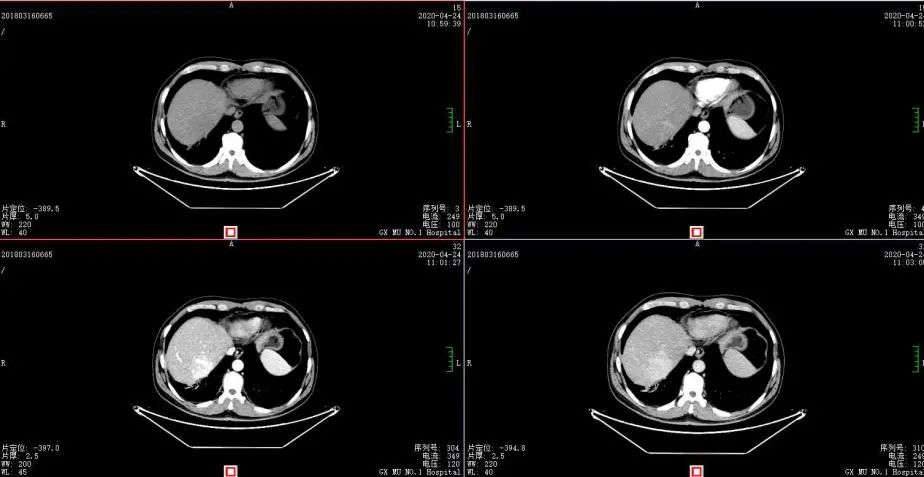

△2018-3-19基线CT

2018-11-14 CT(8周期化疗后):PD?

△基线水平

△治疗后

2020年4月复查:持续PR

增强CT示:肝硬化

肝异常强化灶

考虑酒精性肝硬化可能性大,未基线使用替吉奥维持治疗。